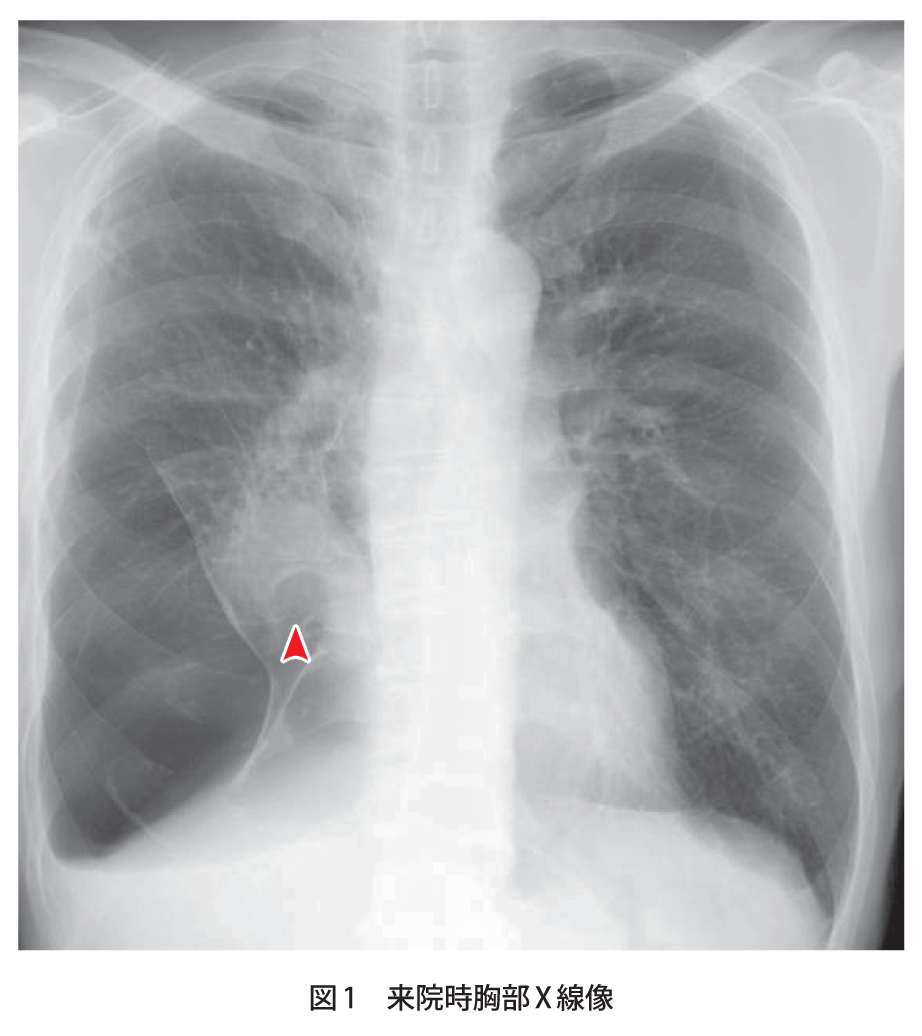

無気肺の存在診断は、画像検査で、含気を失った罹患肺葉は濃厚なくさび型陰影として認められる。典型的な肺葉性無気肺の場合、図に示したような所見をとる( 図表 > 図表 > 図表 > 図表 > 図表 > 図表 > )。 。 また、無気肺によって生じる位置の偏位や濃度の変化を来す無気肺周辺の変化を>画像所見 : 胸部単純 x 線写真正面像では右下肺内側が暗くなっており、右心第 2 弓の輪郭が不明瞭(シルエットアウト)。 側面像では肺門部から前肋横角に向かう紡錘形の陰影(↓)がみられる。 >診断 : 中葉無気肺 >解説 : 無気肺化した中葉は正面単純写真では右心第 2 弓を底辺と 肺の場所をct画像でチェック! 縦隔条件(じゅうかくじょうけん) 30歳代男性の造影剤を用いていない単純ctの冠状断像(前から見た画像と思ってください)です。 さらにこの肺以外の様々な臓器が写っている条件を縦隔条件と言います。 左右の真っ黒な肺 はいずれも左右の肋骨などが作

症例 1 80歳代後半 男性